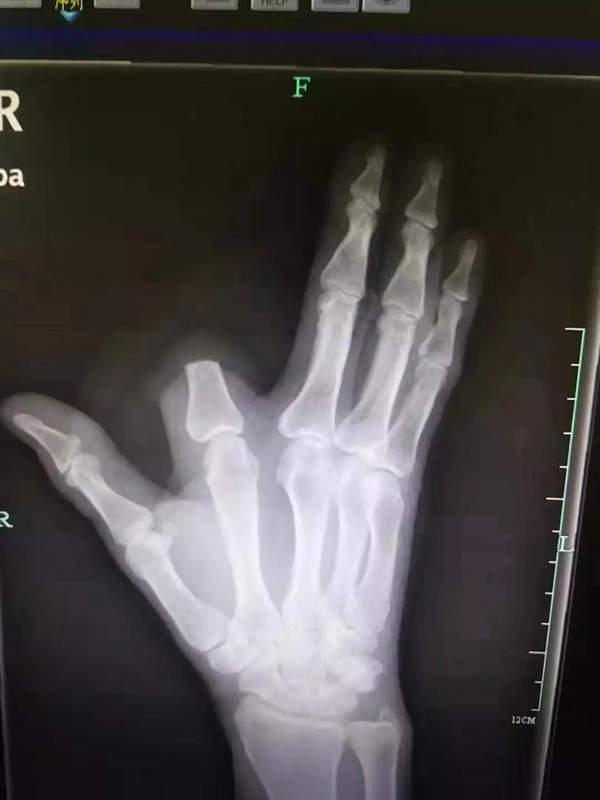

近日,贵州一位60多岁的张先生在上山干活的时候,食指就意外被五步蛇给咬伤了,他十分担心自己会像电视剧里演的一样,瞬间毒发身亡。

所以,为了避免自己在走动后加速血液流动,导致病毒加速扩散,张先生只能忍痛选择自切手指的方式,挽救自己的生命。

遗憾的是,张先生还将断指就地丢弃,一个人慌里慌张地去了市中医院挂急诊。经过医生一系列检查,医生认为张先生这种方法没有必要,本来断指尚可以再植,如今,只能由骨科医生手术处理断指残端,张先生也将留下终身残疾。